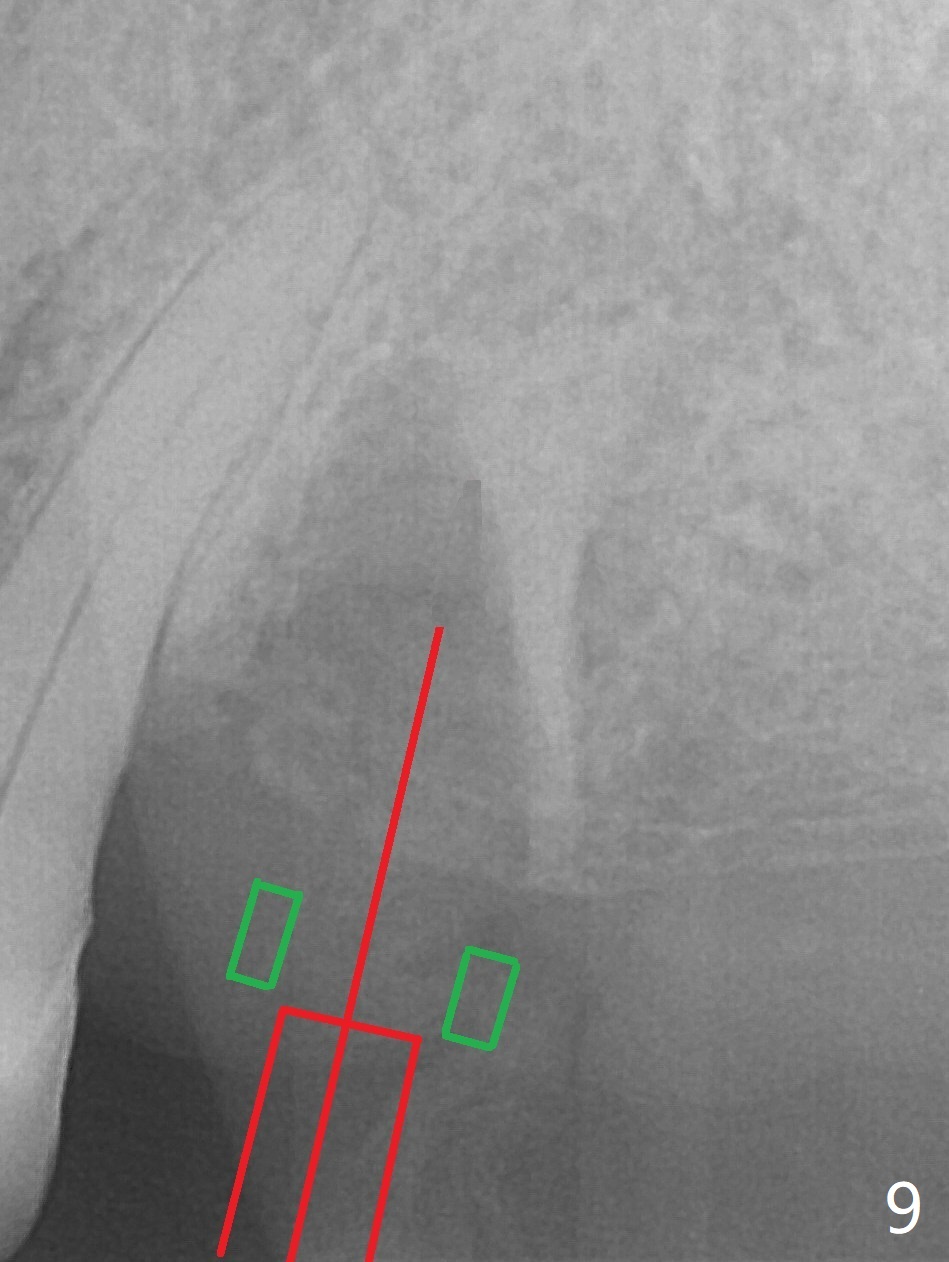

After extraction of the tooth #13 residual root, the bone in the distal wall of the socket looks white. Intraop PA rules out root structure (Fig.1 *). Osteotomy is conducted according to drill sequence. Bitewings are taken to check implant placement level (Fig.2,3). Following implant level adjustment and healing abutment installment (Fig.4,5 (*: bone graft)), the implant at #13 is found to be close the root of #12 (Fig.6 *), i.e., not parallel to the implant at #14. Introspectively, 2.2x10 mm drill seems to be long. When it touches the bone, the cylinder portion of the drill (Fig.7 red) does not engage into the sleeve (green). When it goes into the bone, it may have been deflected mesial due to the slope of the distal wall of the socket (hard bone, Fig.8 open arrow)). If a shorter drill (such as 2.2x7.3 or 8.5 mm) were used (Fig.9), the deflection would be minimal if drilling is slow (Fig.10). CT taken 1 week postop shows that the implant at #13 is approximately 1 mm near the root of the tooth #12, but the neurovascular bundle to the latter seems not to have been interrupted (Fig.11,12). The buccopalatal trajectory at #14 is within normal limit (Fig.11,13 (B: buccal)). There is no periapical radiolucency at #12 five months postop (Fig.14). However the cemented abutments are incompletely seated (<). The patient is reluctant to return for impression 17 months postop (due to coronavirus); with attention, the same abutment at #13 is reseated completely; an abutment with longer cuff and narrower diameter is also seated completely (Fig.15).